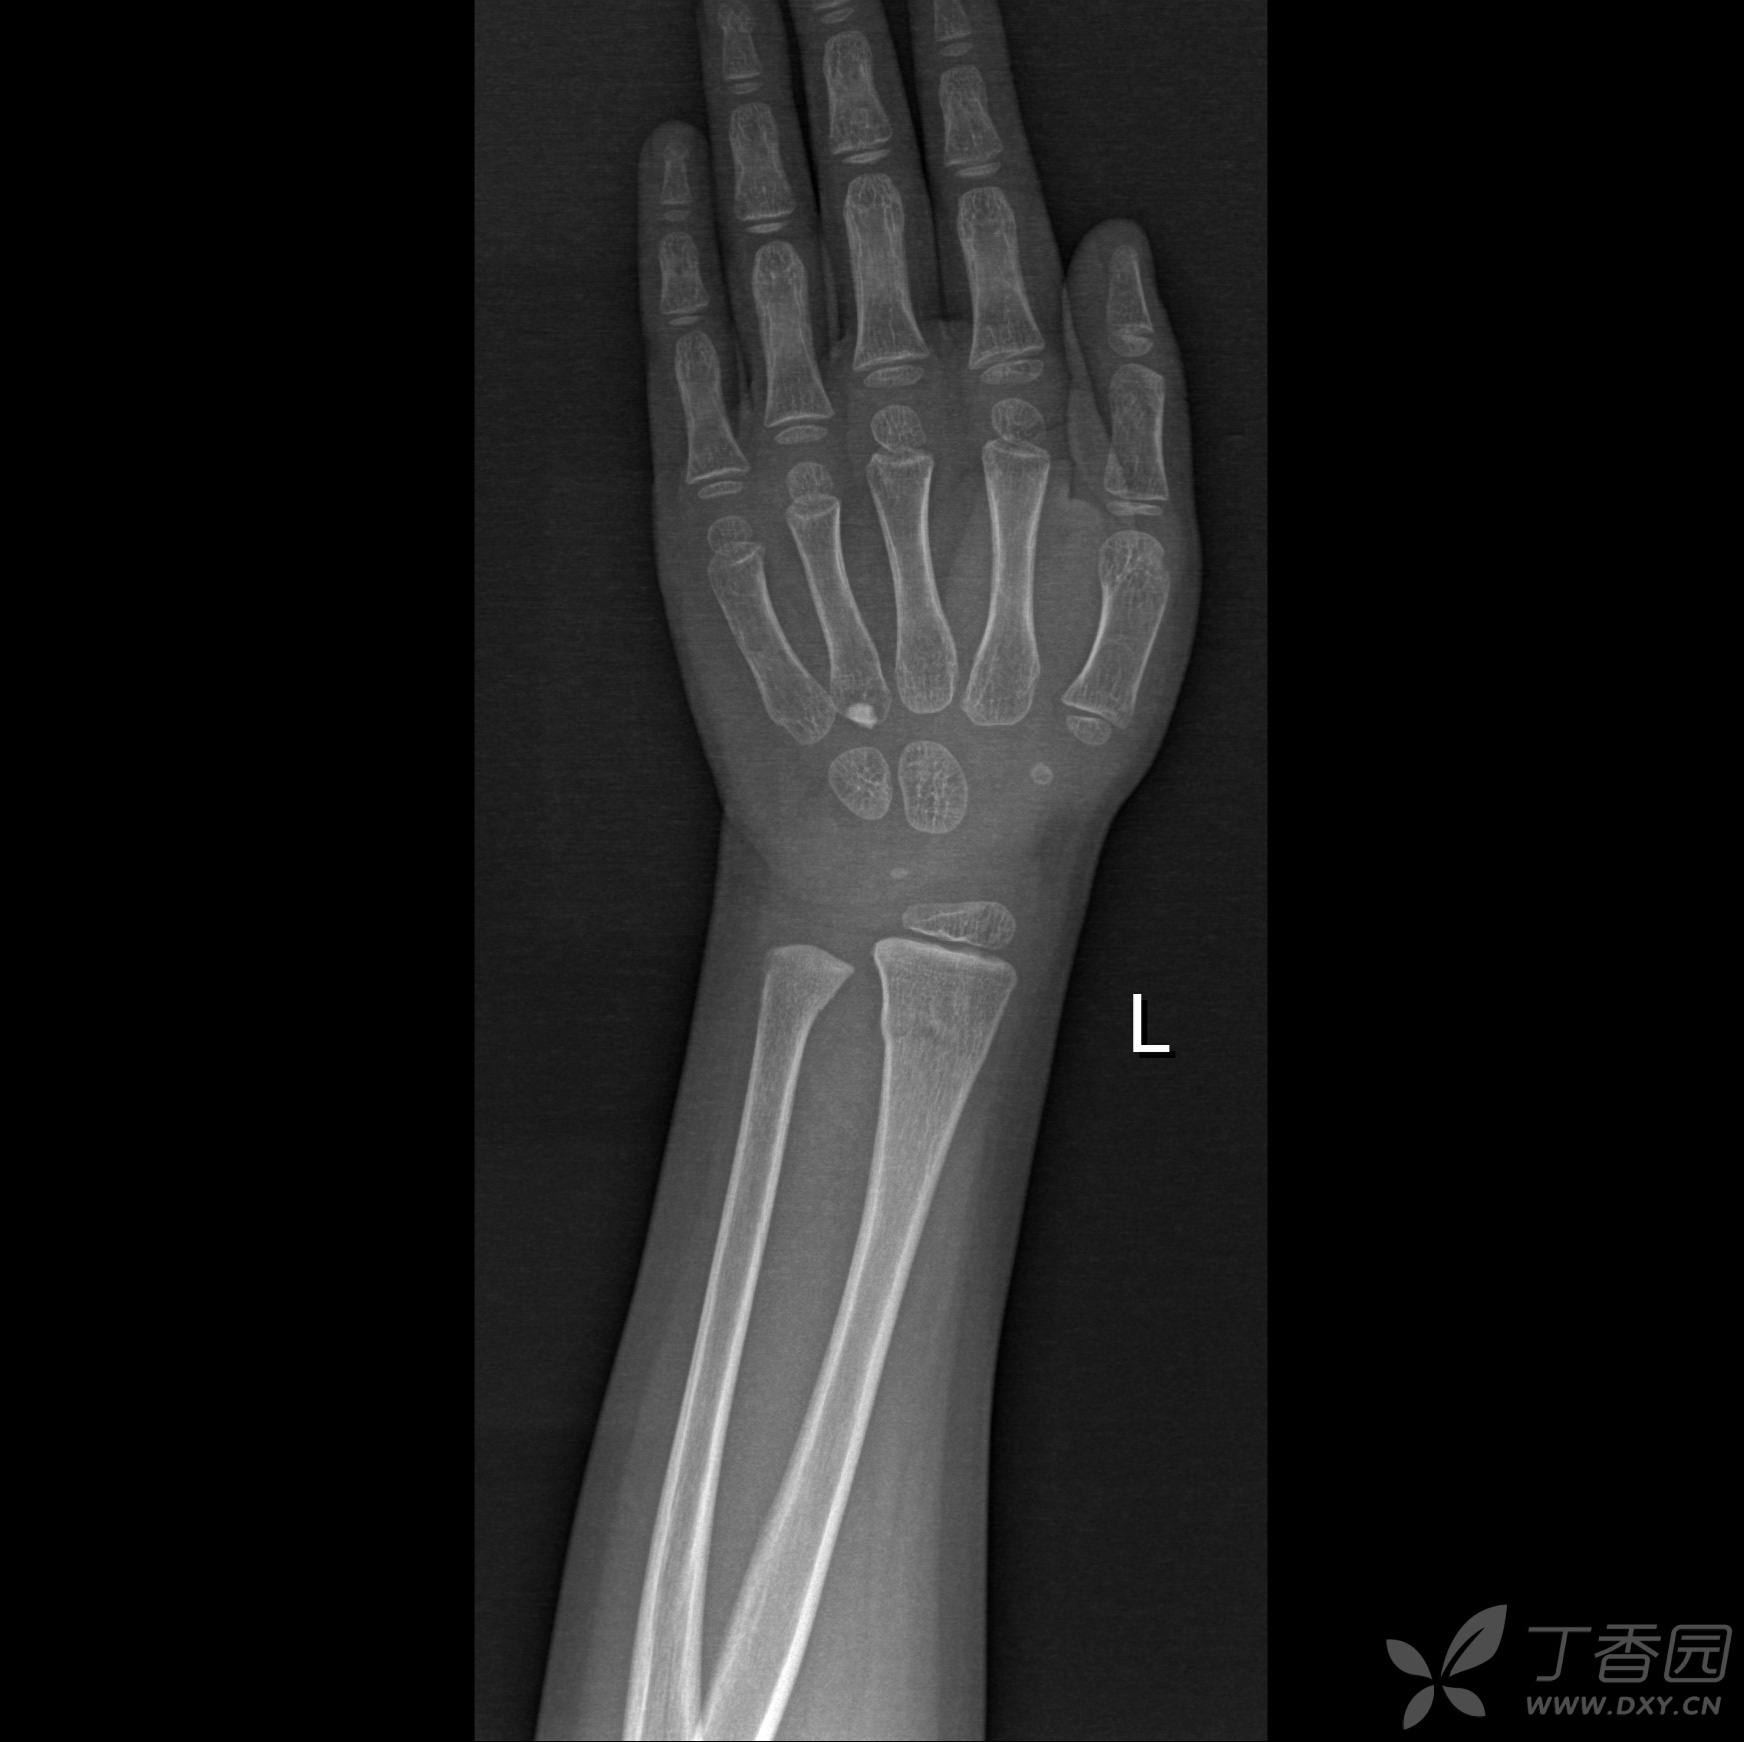

七旬老妪 散步滑倒 左手撑地 左腕剧痛 急至我院 尺桡双折 - 抖音

左腕片

左腕关节x线片左桡骨远端骨折并移位.